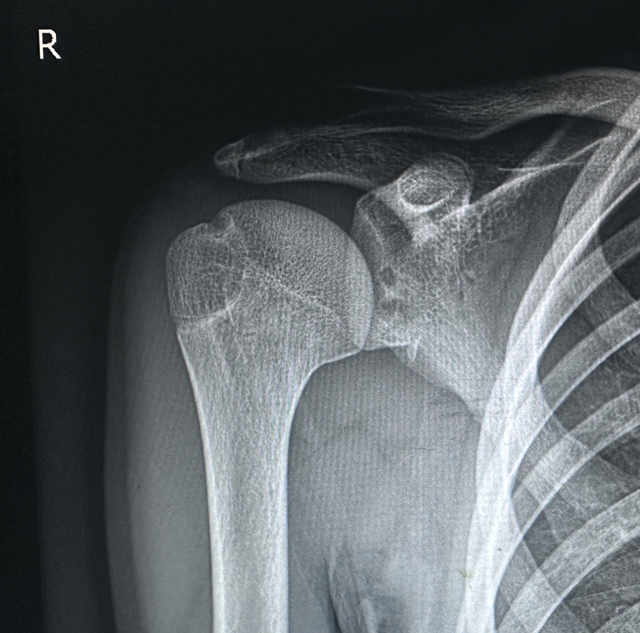

术前检查

经详细检查,暴丁溯副教授发现涵涵右侧肩关节复发性前脱位术后再脱位、冈上肌损伤修复术后再撕裂、右肩陈旧性bankart损伤(指盂唇前下方在前下盂肱韧带复合体附着处的撕脱性损伤)、右肩Hill-Sachs 损伤(指肩关节前脱位时,肱骨头后外侧与肩胛盂前缘撞击导致的压缩性骨折)……属于复发性肩关节脱位,体征明显、症状严重。

术后复查